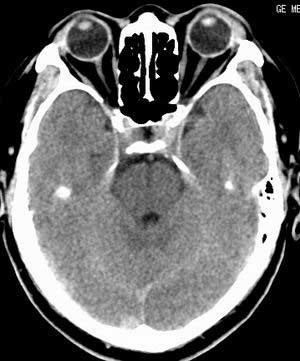

患者男,58岁。耳爆震伤后耳聋2年余,而后双耳道肿胀,间断性流脓。近一月来头痛、恶心、呕吐,右眼红痛,不能入眠。

在平扫时,见右侧枕骨下方小脑半球表面带状模糊稍高密度影,考虑为耳源性脑内感染。

平扫右侧岩骨与枕骨交角内侧脑质内见淡片状密度增高影,内缘清晰。增强图象上未见明显显示。

考虑:1)伪影可能,建议复查头ct平扫。

2)加照头ct骨窗,以显示乳突气房内是否有病变。

右枕颅骨内板下高密度应该是窦的变异,和其症状应该无关,根据病史另找原因吧。[em16]

条状高密度为小脑幕吧

正常平扫片,右侧为血管影。

条状高密度为小脑幕

横窦乙状窦。